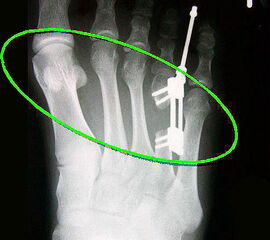

Das im Folgenden vorgestellte Operationsverfahren beschreibt die Kallusdistraktion von Metatarsalia nach den Prinzipien von Ilisarov 21 unter Verwendung eines internen, winkelstabilen Titan-Minifixateur (Klauser 2009). Der interne Distraktor ermöglicht während der Distraktions- und der Durchbauungsphase aufgrund seiner hohen Stabilität je nach Modell (18 mm, 23 mm) eine Verlängerung von bis zu 25 mm. Nach interner Anlage des Minifixateurs, meist lateral, kann über eine kontinuierliche Kallusdistraktion der Metatarsalebogen unter frühzeitiger Mobilisation im Gips oder Short-Walker rekonstruiert werden 15. Über einen interdigital und transcutan ausgeleiteten Aktivatorstab wird die Distraktion vom Patienten selber täglich morgens und abends durchgeführt. Zusätzlich vorliegende Strahlpathologien, wie zum Beispiel eine verkürzte Strecksehne oder ein kontraktes Metatarsophalangealgelenk können im Rahmen der Erstoperation ebenso therapiert werden wie z.B. ein Hallux valgus, ein Hallux valgus interphalangeus und/oder ein Digitus quintus varus (Klauser 2009). Nach Rekonstruktion des Metatarsalebogens wird in einem zweiten, kleinen Eingriff der Aktivatorstab über eine Spezialpinzette diskonnektiert und entfernt, wobei der Distraktor als interne Fixation belassen wird. Die Entfernung des Distraktors erfolgt in der Regel nach 9 – 12 Monaten, da es sich meist um angeborene kindliche Fehlbildungen handelt (Brachymetatarsie) und eine operative Intervention frühzeitig im Kindesalter erfolgen sollte (Klauser 2009).

Meist kam ein 18mm Minifixateur zur Anwendung und ausnahmslos wurde er lateral am Metatarsale implantiert. Bis auf das Metatarsale 5 wurden vom Autor alle weiteren Metatarsalia (MT1 – MT4) isoliert oder kombiniert verlängert. In 7 Fällen wurde eine simultane Verlängerung zweier Metatarsalia (2x MT1 und MT4, 4x MT3 und MT4, 1x MT2 und MT3) vorgenommen. Bei einem Großteil der Patienten musste eine Strecksehnenverlängerung entweder im Rahmen der Erstoperation oder im Rahmen der Aktivatorentkopplung vorgenommen werden. In neun Fällen (ausnahmslos bei Erwachsenen > 30 Jahre) sogar 2x sowohl während des Erst- als auch Zweiteingriffes. Annähernd regelhaft sind bei den eben genannten Eingriffen Arthrolysen des Metatarsophalangealgelenks des betroffenen Zehenstrahls erforderlich, da durch die Distraktionsverlängerung eine hohe Kompression auf das jeweilige Grundgelenk entsteht.